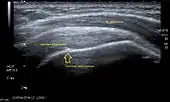

Ultrasound

There are several advantages of ultrasound. It is relatively cheap, does not emit any radiation, is accessible, is capable of visualizing tissue function in real time, and allows the performance of provocative maneuvers in order to replicate the patient’s pain.[26] Those benefits have helped ultrasound become a common initial choice for assessing tendons and soft tissues. Limitations include, for example, the high degree of operator dependence and the inability to define pathologies in bones. One also has to have an extensive anatomical knowledge of the examined region and keep an open mind to normal variations and artifacts created during the scan.[27]

After the introduction of high-frequency transducers in the mid-1980s, ultrasound has become a conventional tool for taking accurate and precise images of the shoulder to support diagnosis.[29][30][31][32][33]

Adequate for the examination are high-resolution, high-frequency transducers with a transmission frequency of 5, 7.5, and 10 MHz. To improve the focus on structures close to the skin an additional "water start-up length" is advisable. During the examination the patient is asked to be seated, the affected arm is then adducted and the elbow is bent to 90 degrees. Slow and cautious passive lateral and/or medial rotations have the effect of being able to visualize different sections of the shoulder. In order to also demonstrate those parts which are hidden under the acromion in the neutral position, a maximum medial rotation with hyperextension behind the back is required.[34]

To avoid the different tendon echogenicities caused by different instrument settings, Middleton compared the tendon’s echogenicity with that of the deltoid muscle, which is still lege artis.[35][36]

Usually the echogenicity compared to the deltoid muscle is homogeneous intensified without dorsal echo extinction. Variability with reduced or intensified[37] echo has also been found in healthy tendons. Bilateral comparison is very helpful when distinguishing and setting boundaries between physiological variants and a possible pathological finding. Degenerative changes at the rotator cuff often are found on both sides of the body.[38] Consequently, unilateral differences rather point to a pathological source and bilateral changes rather to a physiological variation.[36]

In addition, a dynamic examination can help to differentiate between an ultrasound artifact and a real pathology.[39]

To accurately evaluate the echogenicity of an ultrasound, one has to take into account the physical laws of reflection, absorption and dispersion. It is at all times important to acknowledge that the structures in the joint of the shoulder are not aligned in the transversal, coronal or sagittal plane, and that therefore during imaging of the shoulder the transducer head has to be held perpendicularly or parallel to the structures of interest. Otherwise the appearing echogenicity may not be evaluated.[40]

Longitudinal ultra sonography of the supraspinatus tendon |

Transversal ultra sonography of the supraspinatus tendon |